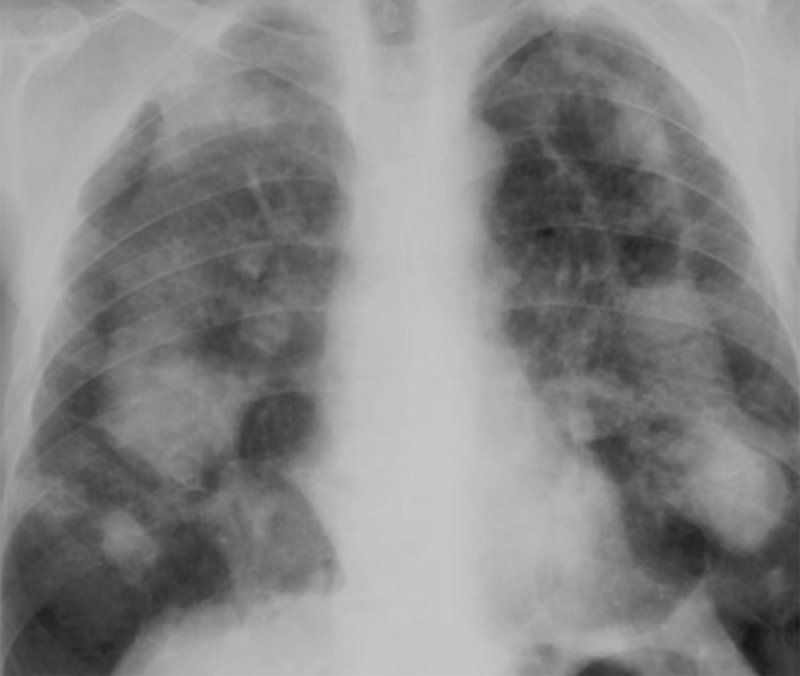

Рисунок 2. Силикоз I-II стадии. В обоих легких определяются многочисленные мелкие узелки, размером 2-3 мм. Изменения преобладают в средних отделах легочных полей